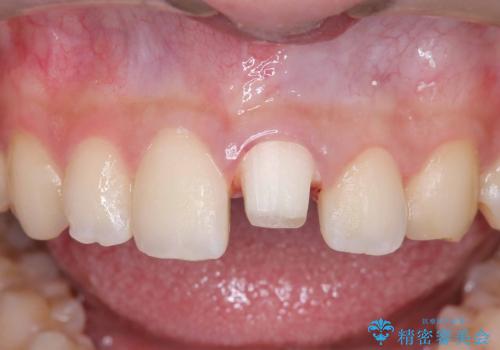

サーフィンで前歯をぶつけて歯が欠けた|かかりつけ医で治療困難と言われ当院へ来院|VPT(生活歯髄療法)で神経を保存|前歯の見た目も改善

- 歯冠破折により点状露髄を認めました。破折から1週間以内であったこと、また歯髄診断により生活反応が良好で保存可能と判断したため、VPT(生活歯髄療法)を行い神経の保存を試みました。